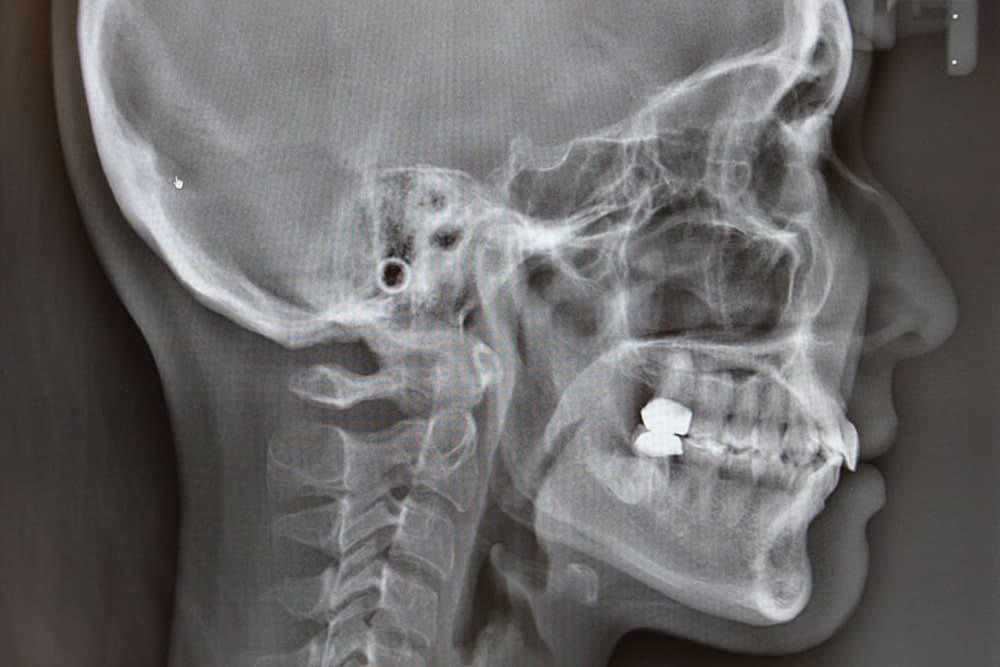

精密検査

インビザラインによる矯正治療をご希望される方は、まずレントゲン・歯型・口腔内写真などの各種検査を行い、適切な治療計画を作成していきます。

短期間の矯正治療が期待できる「インプラント矯正」にも対応

一般的なインプラントではなく、矯正用のインプラントを駆使した矯正方法です。矯正治療専用のスクリュー(チタンでできたねじ状のもの)を骨に埋め込み、そこを支点に歯に力をかけていく矯正法で、しっかりと力をかける土台を作ることで、治療期間を6~8カ月短縮できることもあります。 また、インプラントはお口の中の後方に埋め込むため、ほとんど目立ちにくいというメリットがあります。矯正用のインプラントを埋め込む際は局所麻酔を使用しますが、治療時間は10~20分程度です。インプラントは非常に細いものを使用しますので、ほとんど痛みや腫れはなく、矯正治療終了後に傷跡が残ったりすることもありません。